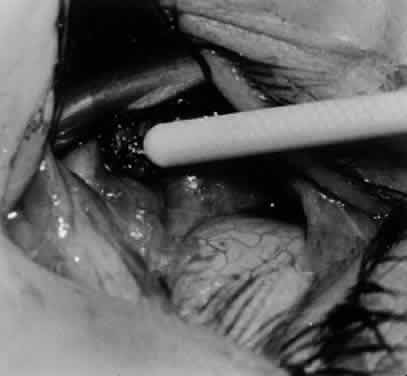

Fig. 5. The Stevens hook is placed adjacent to the posterior edge of the inferior oblique muscle and rotated as the inferior oblique muscle is drawn into the operative field. A forceps is used to retract the redundant Tenon's capsule, encapsulated fat, and intermuscular septum as the muscle is drawn further into the operative field with the Stevens muscle hook.

Fig. 6. The Westcott scissor is used to open the intermuscular septum along the posterior border of the inferior oblique muscle. Care is taken to cut adjacent to the tip of the Stevens muscle hook. This incision is important because it helps to avoid damaging the Tenon's capsule and releasing fat, which leads to the adherence syndrome and postoperative hypotropia.